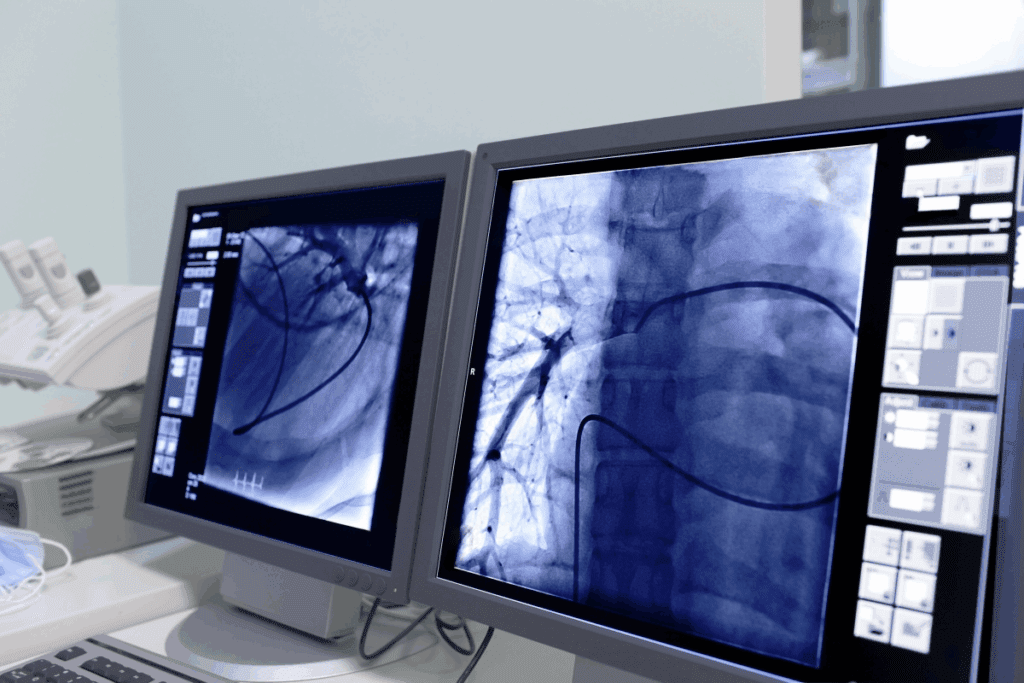

Another big difference is the use of image guidance. Tools like fluoroscopy and MRI help doctors see what they’re doing in real-time. This precision is hard to match with traditional surgery.

Angiography lets us see inside blood vessels. We use a contrast agent to spot problems like blockages. This tool is vital for planning treatments.

Angioplasty and stenting open blocked blood vessels. A balloon is used to widen the vessel, and a stent keeps it open. This method is often used for peripheral artery disease.